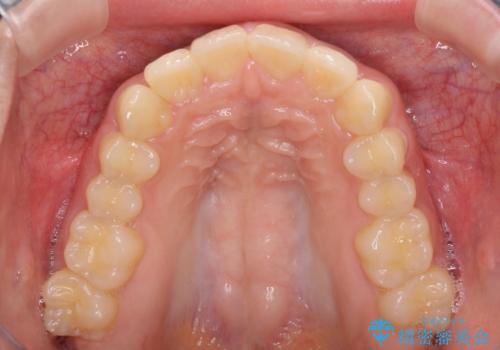

就職前にきれいな歯並びにしたい 大学生のインビザライン矯正

- 就職するまでに歯並びをきれいにしたいとのことで来院された患者様です。

前歯の叢生を気にしていましたが、極力突出感を改善できるようにすることとし、インビザラインにて矯正治療を行うこととしました。

改善の期待できない口元の突出感改善を希望されたため、いたずらに治療期間が延びましたが、きっちりと仕上がりました。